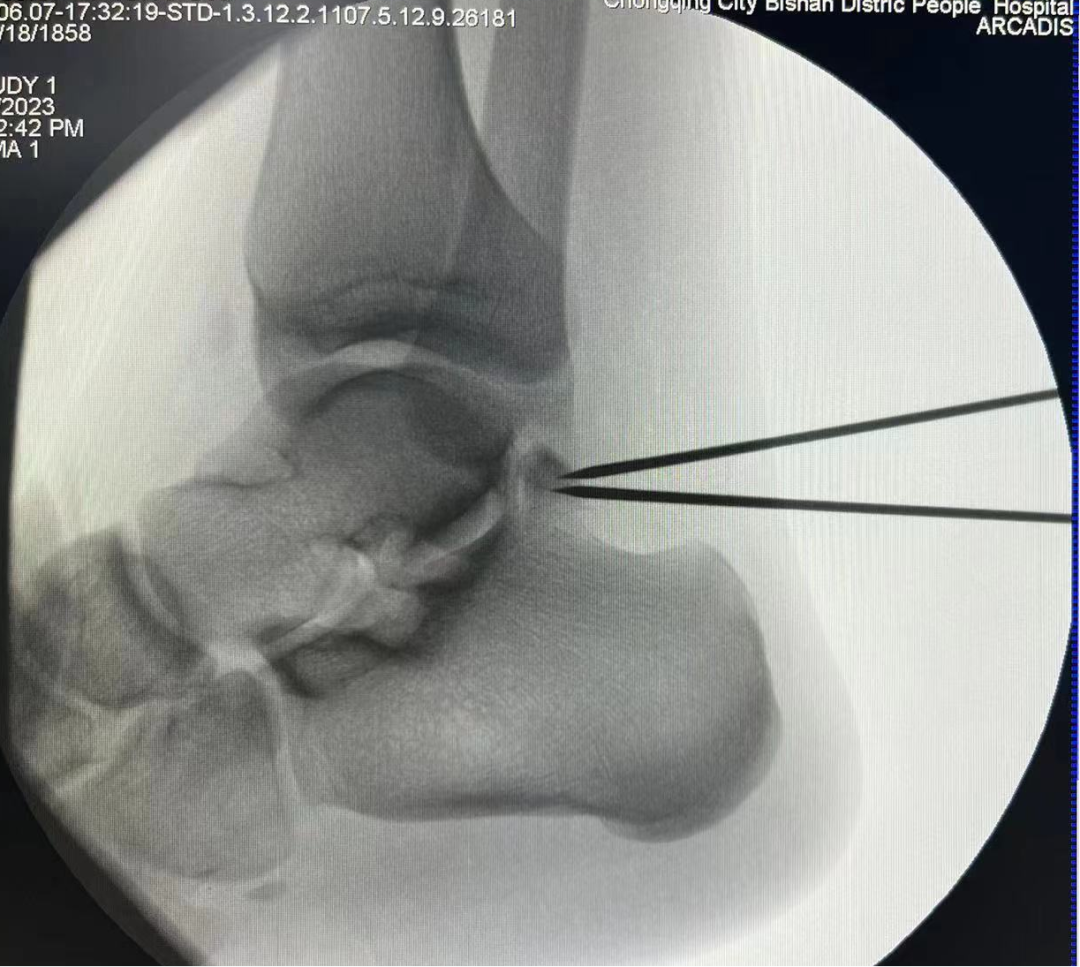

术中C臂定位病灶位置

一位19岁大学生,由于左踝长期疼痛,辗转多家医院症状未缓解,严重影响其学习生活,经人介绍来到我院骨科治疗。骨科副主任(主持工作)彭李华博士为其进行了全面专业的检查,发现为三角籽骨综合症。完善术前检查及准备后,彭李华博士为患者行“踝关节全内镜下清理、松解术”。患者对手术效果满意,已顺利出院。

踝关节镜下手术是一种微创治疗技术,其只有2-3个1cm左右的手术切口,在关节内镜直视下进行手术操作,可以对踝关节进行全方位检查,更直观地发现问题、解决问题。相较于传统手术,其具有创伤小、出血少、恢复快、美观等优点。